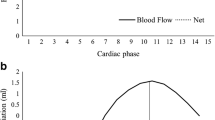

Analysis was performed using GT Flow software. Magnitude image (top left), in-plane vector overlay image (top right), continuous graph of velocity on the voxel (bottom left), and quantitative values (bottom right). We set the voxel contour at the right postcommunicating artery (red dot, arrowheads on the magnitude image) after masking the nonvascular lesion with the dedicated threshold. The in-plane vector overlying the image provides the color-coded flow direction and flow velocity at each voxel (red is fast and blue is slow). The continuous graph can provide the velocity along the cursor in each direction—right to left (RL), anteroposterior (AP), foot to head FH)—during the cardiac cycle. We could then easily detect the flow direction from this information

One neuroradiologist with 10 years of experience and who had interpreted >100 cases of cerebral 4D flow MRI was enlisted to evaluate 4D flow MRI, TOF-MRA, and CTA results in random order. For 4D flow analysis, we first assessed the patency of the graft by 3D pathline imaging. Second, we visually assessed the flow direction in the ipsilateral M1 segment of the middle cerebral artery (MCA) and circle of Willis, the ipsilateral A1 segment of the anterior cerebral artery (ACA), and the posterior communicating artery (Pcom). The flow direction was classified as being in the antegrade and retrograde directions compared to the flow direction of the native flow. This flow direction was determined by 2D in-plane vector map imaging and 3D pathline imaging. When the flow direction was not determined by 3D pathline imaging, we investigated the vector data in each voxel, which corresponds to the vessel seen on TOF-MRA. For each direction—right-to-left (RL), anteroposterior (AP), foot-to-head (FH)—the flow speeds at the target voxels during the cardiac cycle were easily calculated as continuous graphs on GT Flow software (Fig. 1). We chose at least three voxels from the target artery. If all of them had the same flow direction during the cardiac cycle, the flow direction was determined according to these results. If there was a difference between flow results on the voxels, we defined the flow direction in the vessel as “unclear.” As a result, to-and-fro flow was classified as unclear. Third, we quantified the blood flow volume (BFV) of the bypass artery, ICA, and basilar artery (BA). In the 15 patients who underwent both CTA and 4D flow MRI combined with TOF-MRA within 3 months, we measured the diameter of the bypass artery, ipsilateral A1 segment of the ACA, and the Pcom on three slices for each artery and obtained their averages. These slices were identical to that on the 4D flow MRI. We used a dedicated workstation for the analysis (AZE Virtual Place; AZE, Tokyo, Japan).

The flow volume in the BA was not calculated in two patients because it was out of the FOV. There were no apparent artifacts (e.g., motion artifact, susceptibility artifact by implant) that caused MRI deterioration. Representative cases are given in Fig. 2 and Supplementary Movie 1. EC-IC bypass flow was successfully generated in all patients. Nonnative, retrograde flow was observed at the M1 segment of the MCA in 10 of the 19 patients. Retrograde flow at M1 was observed more frequently in patients with a RAG bypass than in those with an STA bypass (p < 0.01) (Table 1). The BFVs of the bypass arteries were significantly higher in patients with a RAG bypass than in those with an STA bypass (3.19 ± 1.13 vs. 1.68 ± 0.97 ml, p < 0.01). In contrast, there was no correlation of the BFV of the contralateral ICA or BA with the type of bypass artery (Table 2). The BFV in the bypass artery significantly (but only slightly) correlated with the arterial diameter of the CTA (p < 0.05, R 2 0.287) and not with that of the TOF-MRA (Fig. 3). One Pcom was hypoplastic on CTA and TOF-MRA. Other arteries were detectable on both CTA and TOF-MRA. In these 29 arteries, the detectability of flow direction in the ipsilateral A1 segment and the Pcom artery were significantly correlated with the arterial diameter seen on TOF-MRA (p < 0.01) but not with that of the CTA (Fig. 4). The cutoff values for the CTA and the TOF-MRA arterial diameters to detect the artery on 4D flow MRI were 2.4 and 1.8 mm, respectively.

Scatterplot of the correlation between the arterial diameter on CTA (a) and time-of-flight (TOF) MRA (b) and the flow volume of the bypass artery. A total of 15 bypass arteries were assessed. Blood flow volume (BFV) in the bypass artery significantly but slightly correlated with the arterial diameter measured on CTA (p < 0.05, R 2 = 0.287) and was not correlated with that measured on MRA